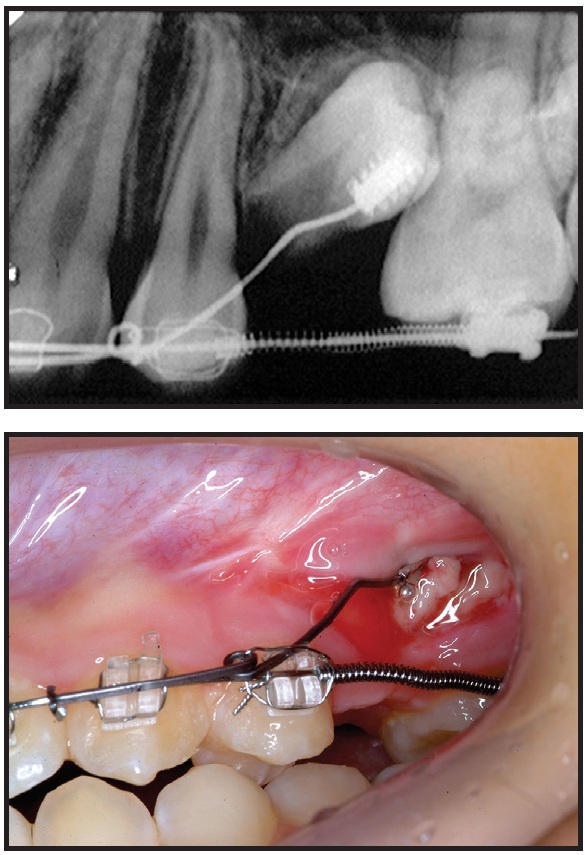

After seven days of healing, orthodontic treatment was resumed. Traction was applied to the twisted stainless steel ligature to bring about full eruption of the tooth. Since the distance between the ligature wire and the main archwire was too short to apply force, a stepdown bend was made in the archwire, and an open-coil spring was inserted between the first molar and first premolar to open and maintain adequate space for the second premolar (Fig. 3). The progress of impacted tooth movement was evaluated monthly (Fig. 4). After three months, to produce more clockwise rotation of the impacted tooth, the metal button was replaced by a minitube and an .016" × .022" TMA*** auxiliary wire was bent and attached (Fig. 5). Three months later, the wire was activated to create an additional rotational moment (Fig. 6).

Fig. 4 Impacted premolar after one (A), two (B), and three (C) months of eruption.